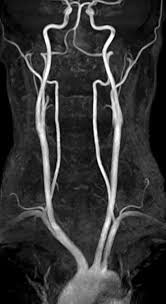

MR Angiography

1. diagnosis of stenosis of carotid bifurcations and intra-cranial aneurysms.

2. suspected venous thrombosis of the chest, abdomen and pelvis

3. pre-surgical workup of carotid endarterectomy or liver transplantation

Problems

1. exaggerated artefacts

2. inferior spacial resolution